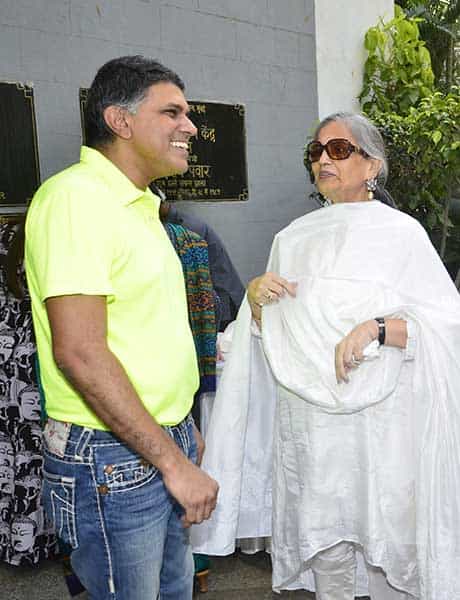

Salma Khan

MUMBAI, INDIA

Surgery Type - Laparoscopic Gastric Bypass(LGB)

Surgery Date - January 23, 2013

Had great difficulty in walking around due to severe pains. In addition she was hypertensive and on regular medications for the same.

One year post operatively she is off all medications.

She loves her new self and the compliments she is being showered with. She is more independent than ever is making the most of new lease on life!!! Previous